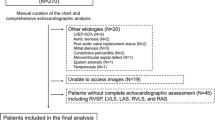

A total of 3205 STEMI patients admitted to the university hospital emergency clinic between 2015 and 2023 were evaluated. The baseline clinical and laboratory parameters of the patients were recorded at admission. A detailed physical examination was also performed with data regarding current smoking status; history of CAD, previous myocardial infarction (MI), previous revascularization (either surgical or percutaneous), hypertension (HT; systolic blood pressure (SBP) > 140 mm Hg and diastolic blood pressure (DBP) > 90 mm Hg in more than one measurement or under antihypertensive therapy); diabetes mellitus (DM); family history of CAD and hyperlipidemia (HL); and noncardiac diseases, such as active or chronic infection, cancer, chronic obstructive pulmonary disease, chronic autoimmune and systemic inflammatory disease, chronic kidney or liver pathology. The current use of antiplatelet drugs, betablockers (BBs), statins and angiotensin converting enzyme inhibitors (ACEIs) was also recorded. The Killip class of each patient was recorded after thorough physical examination [9]. According to the Killip classification, classes were defined as the absence of congestive heart failure findings (class I), the presence of S3 gallop or bibasilar rales or both (class II), pulmonary edema (pulmonary rales halfway up the lung fields) (class III), and cardiogenic shock (class IV). Heart rates and systolic and diastolic blood pressure (DBP) were recorded. The 12-lead ECG signal at admission was recorded at a speed and amplitude of 25 mm/s and 10 mm/mV, respectively, by an ECG device (Nihon Kohden, Tokyo, Japan) in the supine position. Electrocardiographic and clinical diagnoses of STEMI were achieved using the current criteria of the fourth universal definition of MI. New, or presumed new, 1 mm or greater ST segment elevation at point J in two or more contiguous leads other than the V2 and V3 derivations were considered to indicate STEMI with ischemic chest pain. For the V2 and V3 leads, the criteria of 2 mm or greater elevation for males ≥ 40 years old, 2.5 mm or greater ST segment elevation for males younger than 40 years, and 1.5 mm or greater elevation for females were applied [10]. The MI patterns were defined as anterior or nonanterior and included inferior, high lateral or true posterior MI. The pain-to-door (PTD), door-to-balloon (DTB) and total ischemia time (TIT) were calculated according to recent STEMI guidelines. The PTD was defined as the time between the onset of ischemic chest pain and admission to the hospital emergency service. DTB was defined as the time between hospital admission and reperfusion that provides coronary flow distal to the occlusion. TIT is the sum of patient and system time delay to wire crossing or lytic bolus [4, 11, 12]. Transthoracic echocardiography was performed at admission to measure the left ventricular ejection fraction (LVEF) and valvular function by an expert echocardiographer in all patients in the left lateral decubitus position (GE Vivid™ 8 Ultrasound Machine; GE Healthcare, Piscataway, NJ, USA). Images of the parasternal long and short axes and apical four- and two-chamber regions were taken according to the criteria of the American Society of Echocardiography [13]. Blood samples were collected from the antecubital vein via admission to measure hemoglobin (Hgb), creatinine kinase-myocardial band (CK-MB), troponin, creatinine, albumin, total cholesterol (TC), low-density lipoprotein (LDL), high-density lipoprotein (HDL) and triglyceride (TG) levels via an autoanalyzer (ARCHITECT c16000 clinical chemistry analyzer; Abbott Laboratories, Abbott Park, IL, USA). The complete blood count, including white blood cell (WBC) and platelet (PLT) counts, was measured using an automated hematology analyzer (CELL-DYN Ruby Hematology Analyzer; Abbott Laboratories). After initial evaluation in the emergency clinic, each patient was promptly transferred to the coronary catheterization unit. Coronary angiography (CAG) was performed through either the femoral or radial artery according to the physician’s discretion. A ≥ 50% stenosis in one of the major coronary arteries was assumed to be significant. The number of diseased vessels with ≥ 50% stenosis was determined angiographically and recorded. The presence of more than one diseased artery in a patient was assumed to indicate multivessel disease (MVD). Thrombolysis in myocardial infarction (TIMI) flow measurements of the culprit artery were performed by two interventional cardiologists and defined as TIMI 0 if there was complete obstruction, TIMI 1 if the contrast agent penetrated the obstruction without distal dyeing, TIMI 2 if the dye perfused the entire artery but with slow flow, and TIMI 3 if the perfusion was normal [14]. The appropriate anticoagulant (70–100 U/kg initial IV bolus of heparin or IV dose of 0.3 mg/kg enoxaparin in patients who received prehospital subcutaneous enoxaparin injection) and antiplatelet treatments (oral loading dose of 300 mg aspirin and 600 mg clopidogrel or 180 mg ticagrelor or 60 mg prasugrel at the physician’s discretion) were started. PCI for the culprit artery and, if needed, complete revascularization were performed according to the current revascularization guidelines [15]. All patients were followed and reevaluated at the fourth week after the incident event. Any cardiovascular death after discharge in one month was considered death and was defined as one-month mortality. Patients with ST elevation in their ECGs due to early repolarization, pericarditis, left bundle branch block, or Brugada syndrome, as well as those who died before coronary angiography after admission to the hospital and those who were treated initially with thrombolytics, were excluded from the study. Patients who could not be reached for re-evaluation after four weeks were also excluded from the study. All patients and their guardians were informed about the study in case of death, and written consent was obtained. The local ethics committee approved the study. The study was conducted in accordance with the Declaration of Helsinki.

A total of 3205 STEMI patients were included in our study. The basic clinical, demographic and laboratory features of the study groups and their comparisons are summarized in Table 1. The median age of these patients was 58 years. A total of 74% of the patient population was male. Fifty-six patients were in Killip class IV at presentation. A total of 1542 of the patients presented with anterior MI. After CAG, 24 patients had a TIMI flow of 0, 72 patients had a TIMI flow of 1, and 226 patients had a TIMI flow of 2. According to the average silhouette method, the optimal number of clusters was determined to be two (Fig. 1). There were 2731 patients in cluster 1 and 474 patients in cluster 2. Patients in cluster 1 were younger than those in cluster 2. There were fewer patients with HT, diabetes, and HL and fewer smokers in cluster 1 than in cluster 2 (P < 0.001 for all). However, the rate of previous revascularization was lower in cluster 2. In cluster 2, patients used more BBs, statins and ACEIs than did patients in cluster 1. Patients in cluster 2 had higher heart rates and SBP than did those in cluster 1. Patients in cluster 2 had higher WBC counts, PLTs and creatine, CK-MB and troponin levels; additionally, they had lower albumin and Hgb levels. Patients in cluster 2 had lower LVEFs. The number of patients with Killip class 4 and TIMI 0 flow was greater in cluster 2 than in cluster (1) Anterior MI was more common in cluster (2) At the one-month follow-up, a total of 255 patients died. Among the patients who died, 147 (5.4%) were in cluster 1, while 108 (23%) were in cluster 2 (chi-square P < 0.01). Survival analysis revealed that cluster 2 had a notably elevated risk of mortality compared to cluster 1 (Fig. 2) (log-rank P < 0.001). Cox proportional hazards regression analysis was performed to evaluate the associations between one-month mortality risk and patient clusters. Cluster 2 was associated with a greater increase in the risk of death than cluster 1 (hazard ratio (HR) = 4.65, 95% CI = 3.63–5.96; P < 0.001). Even after adjusting for age and sex in the Cox proportional hazard model, the statistical significance of the association between clusters and death persisted (HR = 3.51, 95% CI = 2.71–4.54; P < 0.001).